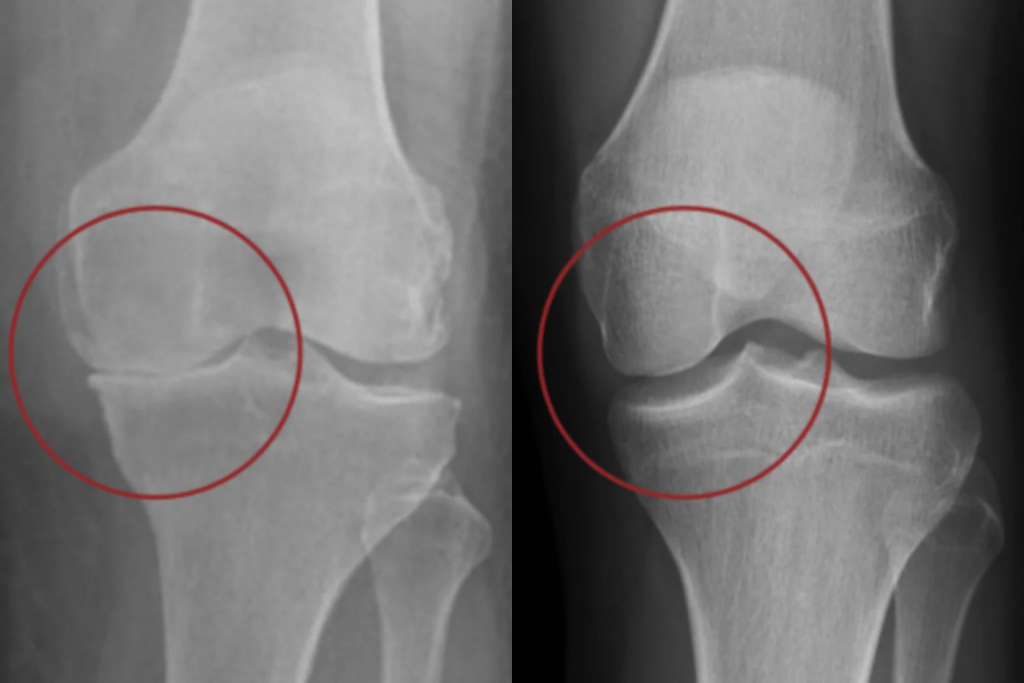

Wissenschaftler haben entdeckt, dass der Rückgang der Gelenkflüssigkeit der zentrale Auslöser für Arthrose ist. Denn die Gelenkflüssigkeit versorgt den Knorpel mit Nährstoffen – fehlt sie, baut sich der Knorpel langsam ab, bis die Knochen schmerzhaft aneinander reiben.

Mit dem Alter nimmt die Gelenkflüssigkeit ab – der Knorpel bekommt keine Nährstoffe mehr und beginnt sich abzubauen.

PetBloom enthält effektive Hyaluronsäure, die diese Flüssigkeit gezielt wieder auffüllt – damit der Knorpel geschützt, versorgt und erhalten bleibt.

Forschung der Universität Utrecht und der Tierärztlichen Hochschule Hannover zeigt, dass mit zunehmendem Alter die Produktion der Gelenkflüssigkeit bei Hunden deutlich abnimmt. Dieser Rückgang führt zu Nährstoffmangel im Knorpel und begünstigt entzündliche Prozesse im Gelenk. Studien zeigen außerdem, dass die Ergänzung mit Hyaluronsäure die Viskosität der Synovia verbessern und die Gleitfähigkeit im Gelenk wiederherstellen kann – ein entscheidender Schritt zur Reduktion von Reibung und Schmerz bei Arthrosepatienten.